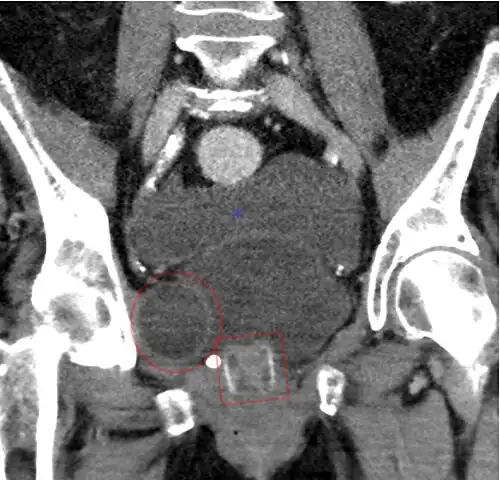

CT-Scan (koronale Rekonstruktion) zeigt ein AMS 800 bei einer Frau -